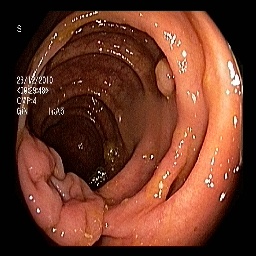

At this stage of the experiments, the generated polyps from PolypConnect (using the EdgeConnect model as the main inpainting model) are prepared for the segmentation evaluation. In total, there are four datasets. Therefore, we train four U-Net [27] models for segmentation. The baseline dataset consists of only real polyp images. The remaining are datasets combining the real and generated polyp images. The first combined dataset consists of 800800800 real and 800800800 generated. The second and third are similar but with 160016001600 and 240024002400 generated polyp images. The models were evaluated on the same validation set of 200200200 real images. The obtained metrics show a clear improvement in all models trained on the additional synthetic data. Results can be found in Table III.

Refer to caption Refer to caption Refer to caption Refer to caption Refer to caption Refer to caption

(a) (b) (c) (d) (e) (f)

Figure 4: Visual comparison of segmentation performance with UNet architecture when synthetic data is used. (a) Input Image. (b) Ground Truth. (c) Baseline (UNet) only with 800 real data (d) real data +800 (e) real data + 1600 (f) real data + 2400.